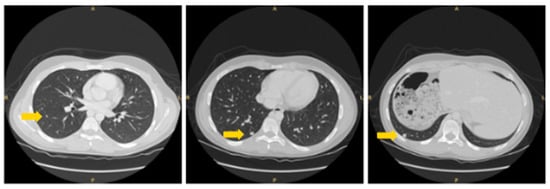

2. Patient Information, Clinical Findings and Diagnostic Assessment

3. Therapeutic Intervention and Outcome